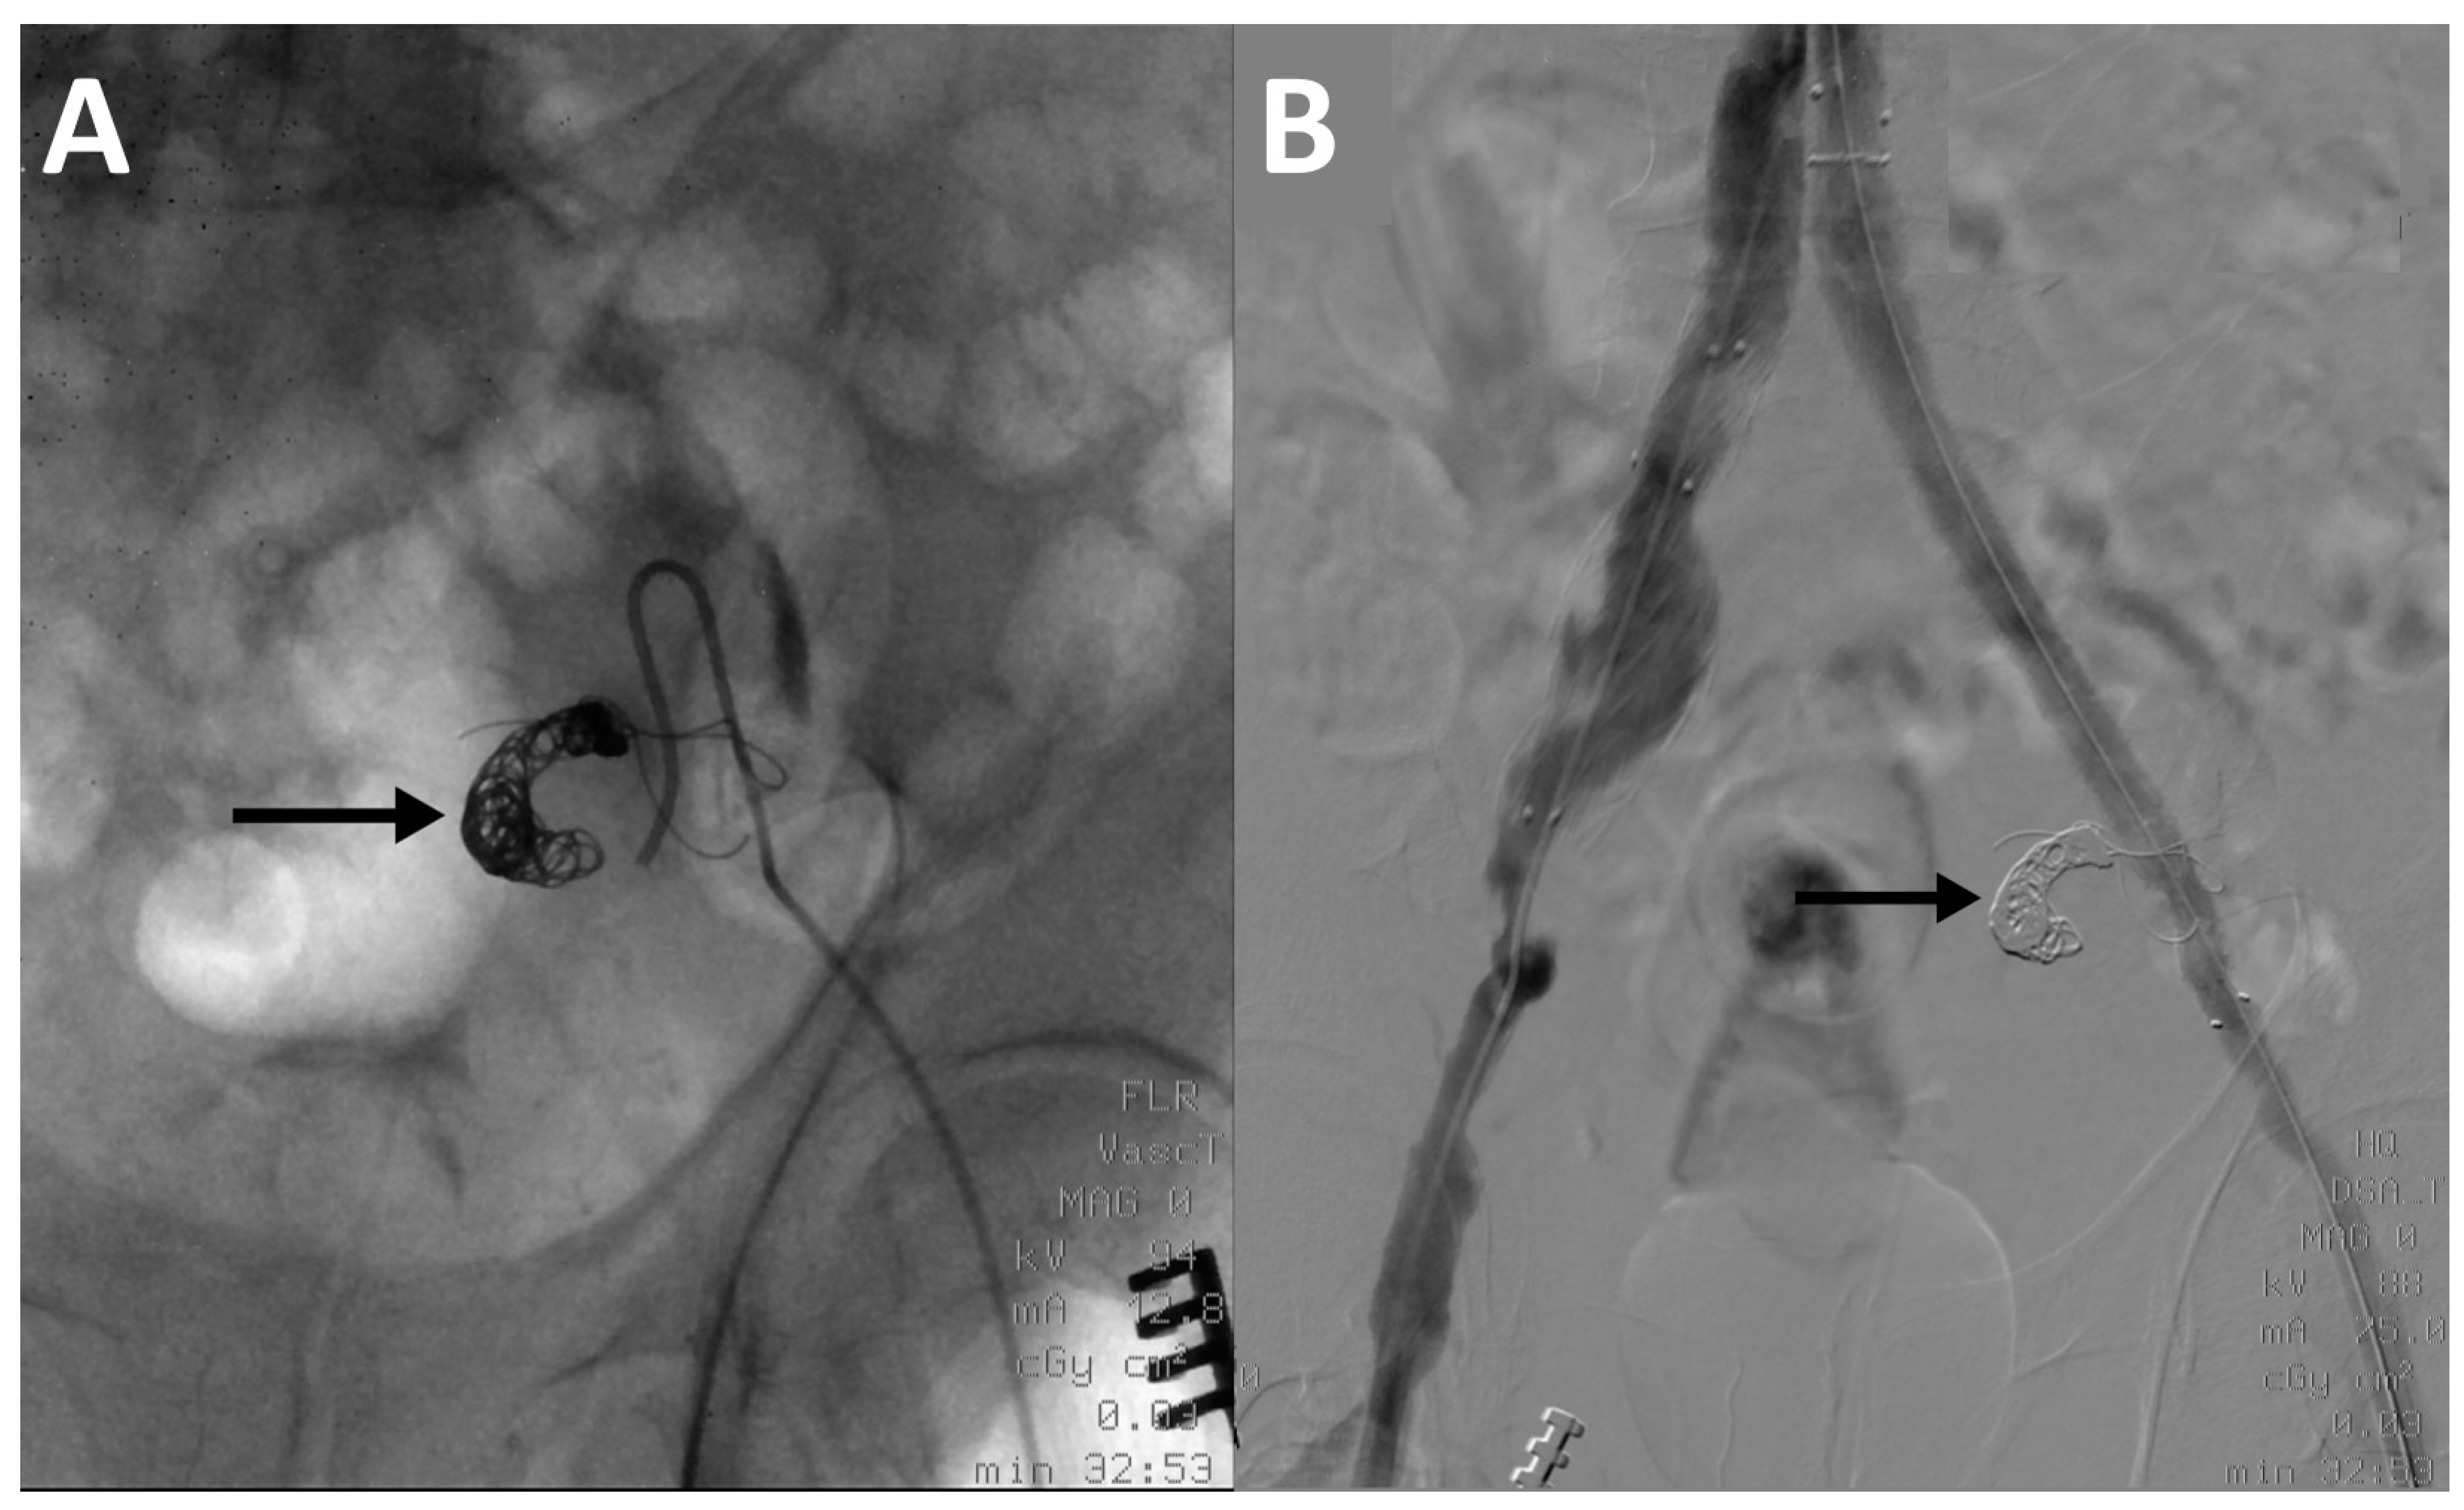

Vascular access was gained via femoral artery. The hypogastric artery was catheterized using a Hook-shaped or a Simmons-shaped (Cordis Corporation, Miami Lakes, FL, USA) catheter. Angiography of the vessel was performed to assess the morphology of the artery and to identify the landing point for coils/vascular plug. For coils positioning, with coaxial technique, a micro-catheter (Terumo Progreat 2.7 Fr, Terumo Corporation, Shibuya, Tokyo, Japan) was moved forward and coils were released into the vessel. The micro-catheter was removed and another angiography was performed to check the correct position of coils. Embolizations performed with vascular plugs required the use of Simmons-shape catheter only and did not involve the use of a micro-catheter (Figure 1).

Figure 1.

(A) Intraprocedural fluoroscopy image of a left ipogastrigc artery embolization with coils (arrows) using a Simmons-shape catheter. (B) Final digital subtraction angiography image at the end of the EVAR procedure showing complete exclusion of the left ipogastrigc artery.